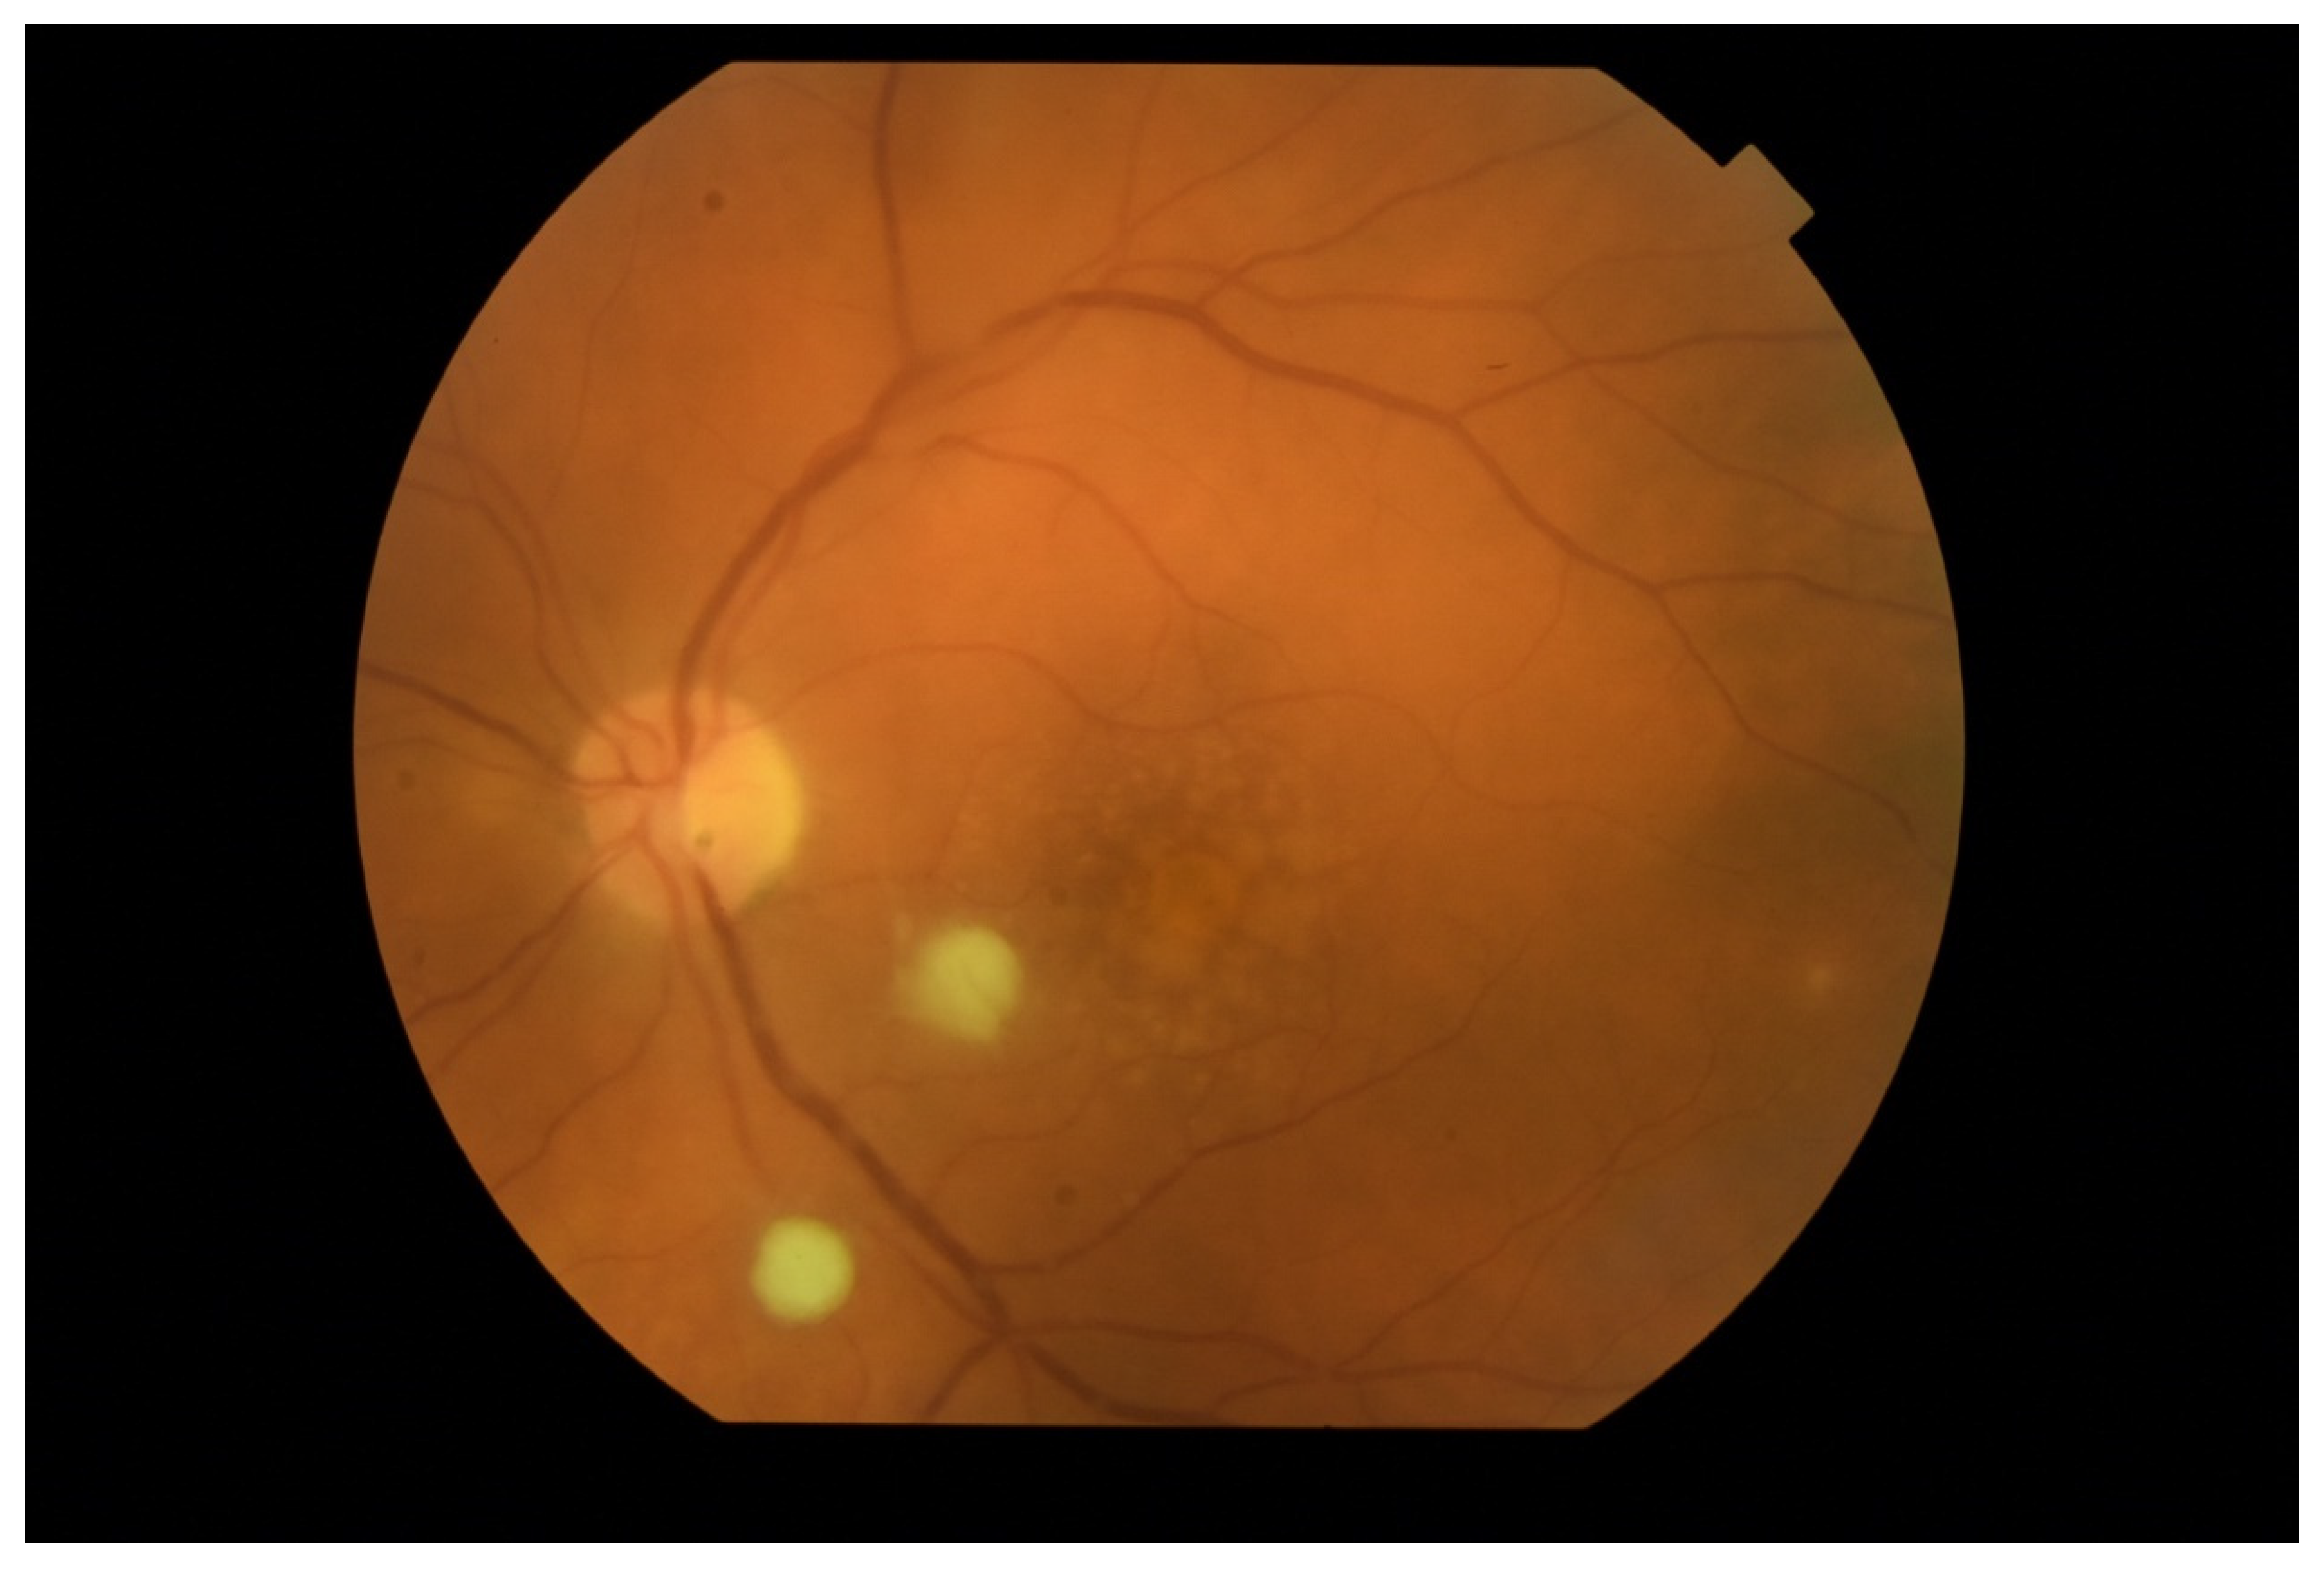

In EE, the transparency of optical media is often reduced. The cornea opacification and Descemet’s membrane folding are common. Tyndall can be found in the aqueous humor, often there is also hypopyon in the anterior chamber (Figure 3 and Figure 4). Inflammation and bacterial toxins are responsible for cataracts development and leakage of the lens proteins into the anterior chamber. In the case of posterior synechiae, the pupil does not respond to mydriatics (Figure 5).

Figure 3.

Tyndall in the aqueous humor causes a blurred image of the iris, especially visible below the pupil. In the lower part of the anterior chamber there is a hypopyon.

Figure 4.

Hypopyon in the anterior chamber. Visible aggregates of inflammatory cells accumulated on the endothelium.